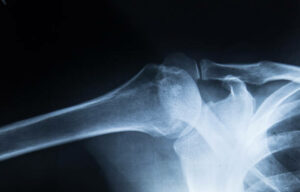

Orthopedics is a branch of medicine that deals with the health and treatment of bones, joints, and connective tissues. If you are a patient suffering from neck pain or back pain or have a sports injury, you could benefit from orthopedic care. Orthopedic doctors are most qualified to treat [Read More]

Arthritis, overuse injuries, and sports injuries are all common conditions that can affect athletes and non-athletes. Being that they are so common, it is important to find an orthopedic facility that specializes in treating them, so you are guided by an orthopedic specialist on how to improve your [Read More]